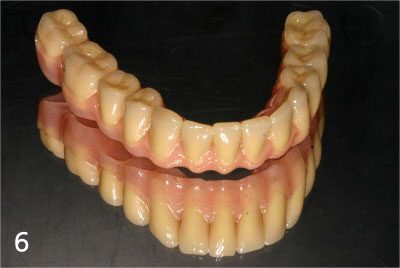

Provisional bridge to use right after placing implants

This is after bonding provisional bridge. Patient can have strong teeth in a few hours